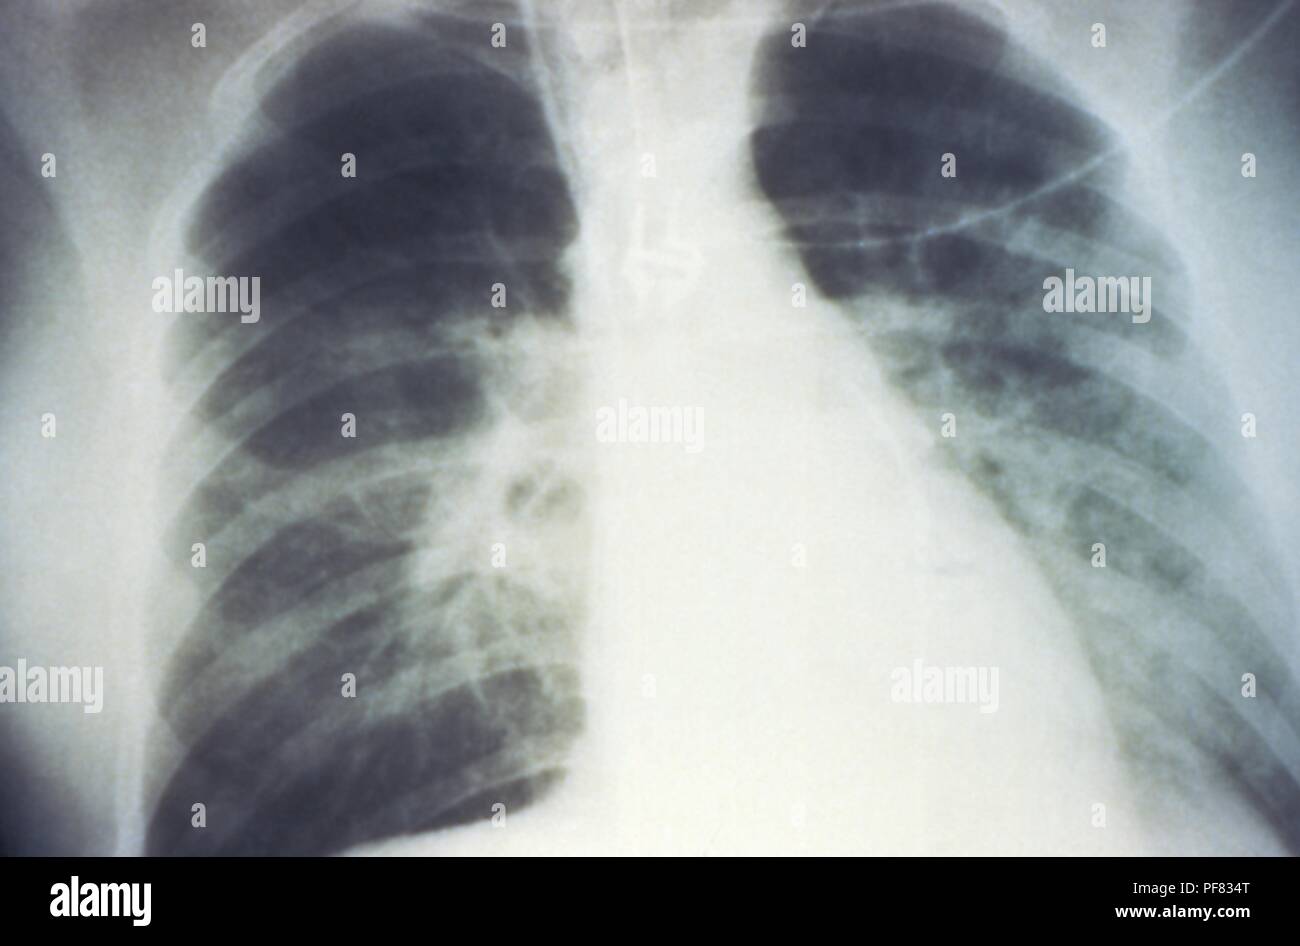

RMPF833F–Mise en scène mi-épanchement pulmonaire bilatéral en raison de syndrome pulmonaire à hantavirus (SPH), révélée dans l'AP La radiographie du thorax, 1994. Image courtoisie Centres for Disease Control (CDC) / D. Loren Ketai, M.D. ()

RMPF8351–Premières étapes de l'épanchement pulmonaire bilatéral en raison de syndrome pulmonaire à hantavirus (SPH), révélée dans l'AP La radiographie du thorax, 1994. Image courtoisie Centres for Disease Control (CDC) / D. Loren Ketai, M.D. ()

RMD0NWAJ–Cette radiographie pulmonaire révèle la mi-monté en raison d'épanchement pulmonaire bilatéral syndrome pulmonaire à hantavirus ou radiologique de la SPLI.

RMPF834T–Mise en scène mi-épanchement pulmonaire bilatéral en raison de syndrome pulmonaire à hantavirus (SPH), révélée dans l'AP La radiographie du thorax, 1994. Image courtoisie Centres for Disease Control (CDC) / D. Loren Ketai, M.D. ()

RMPF834A–Révélé dans le tissu hépatique micrograph image à partir d'un syndrome pulmonaire à hantavirus (SPH) patient, 1994. Image courtoisie Centres for Disease Control (CDC). ()